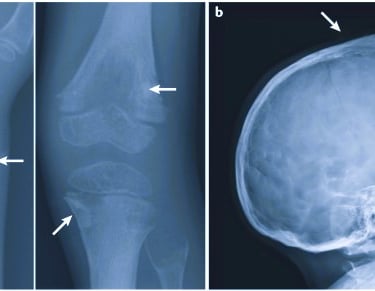

Delayed or impaired bone development

Weak and fragile bones

Pain and fractures